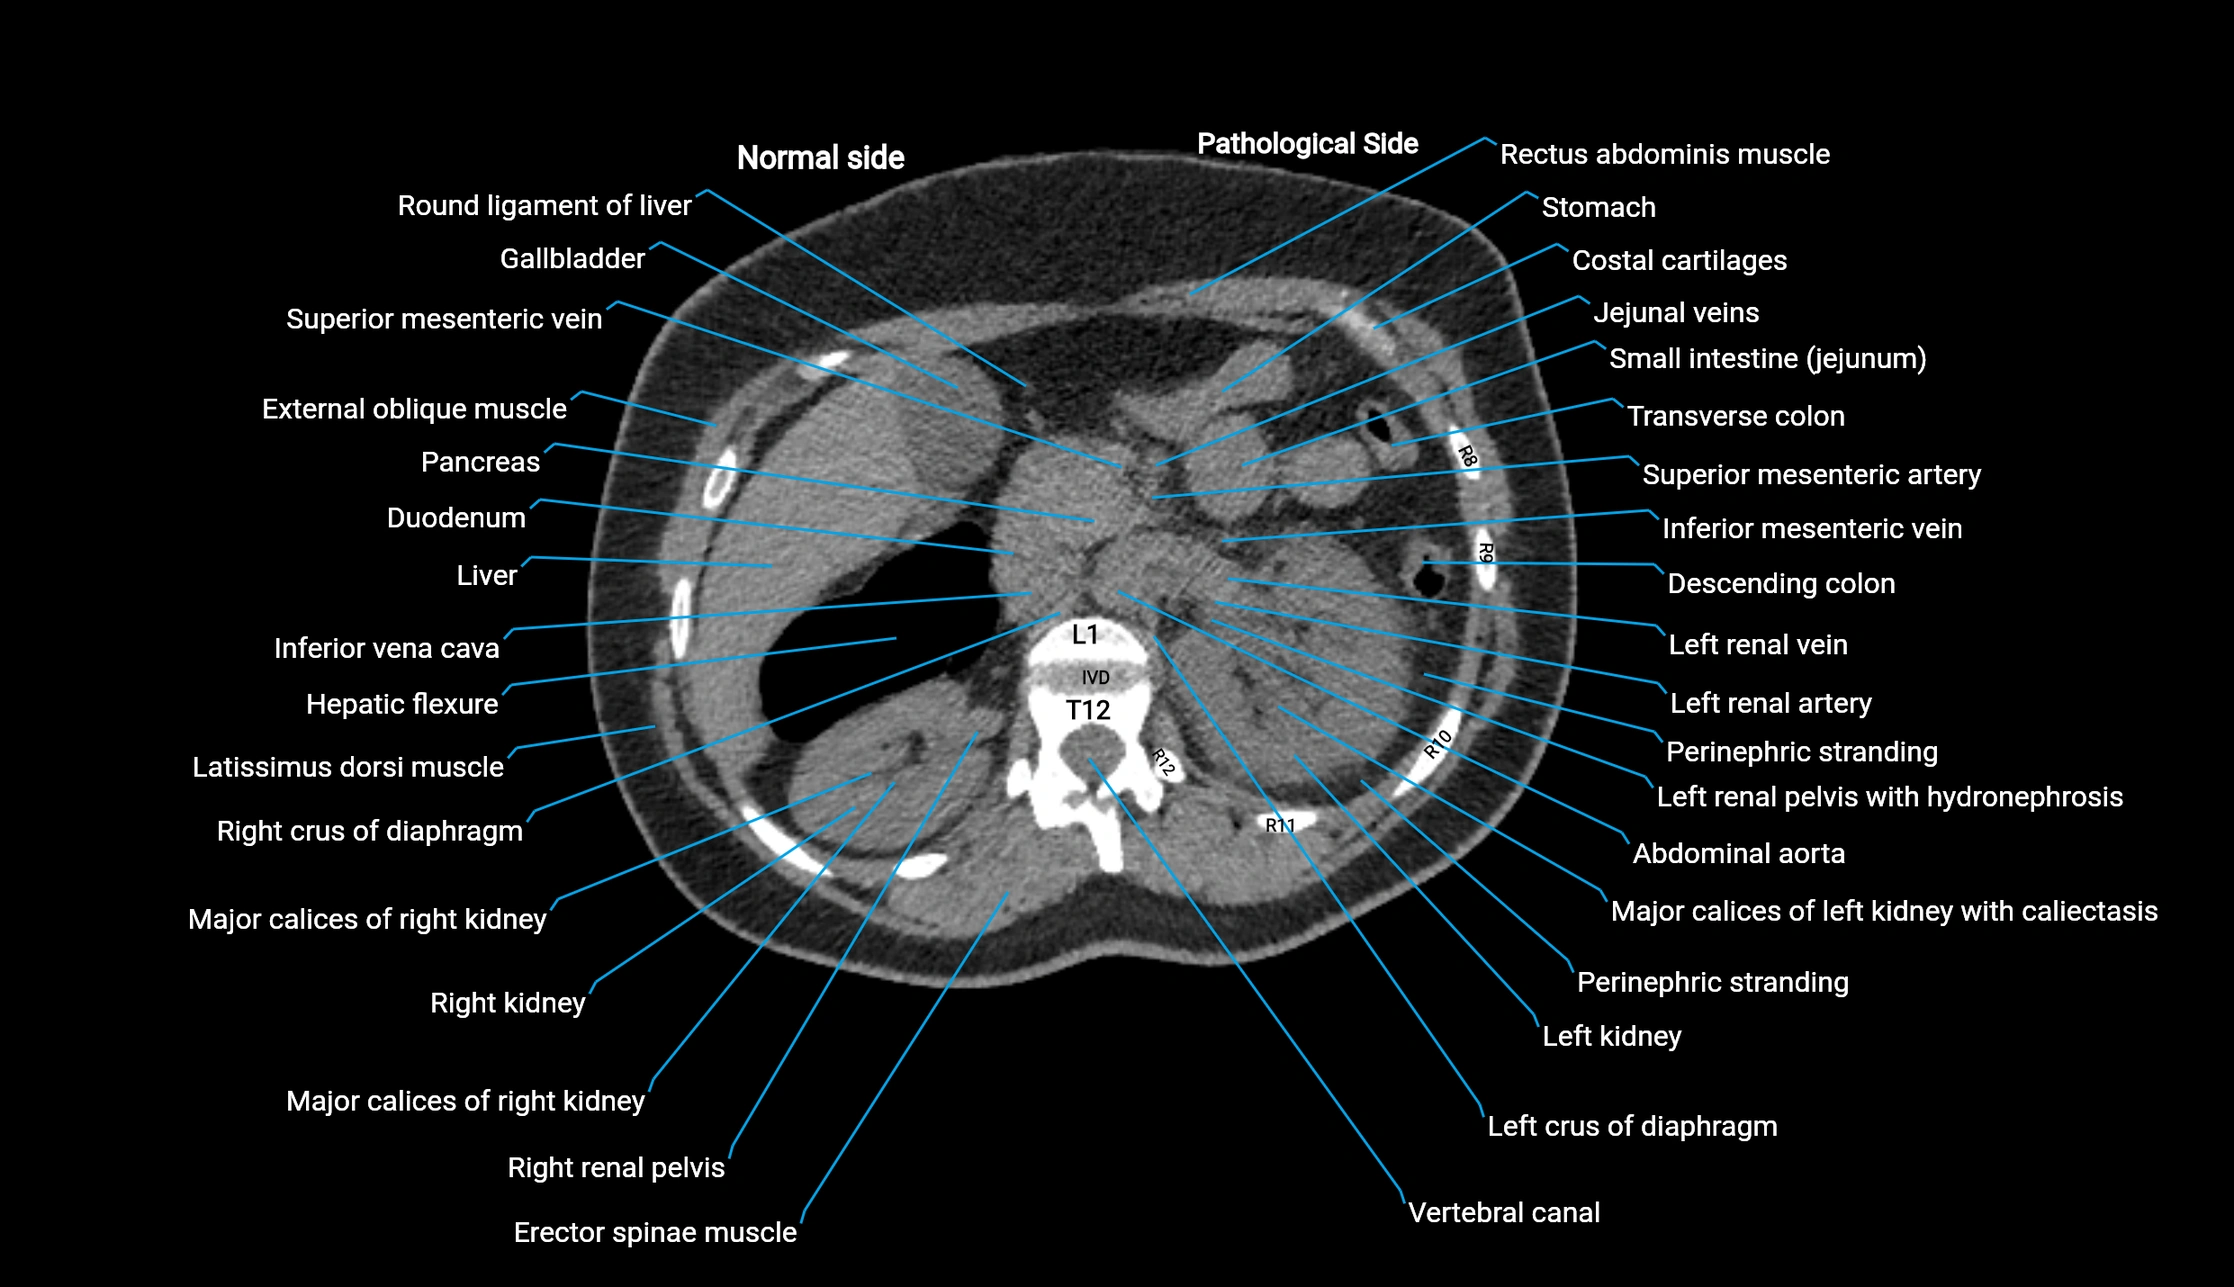

Post-Contrast CT (Contrast-Enhanced CT):

• Portal venous phase:

• Anterior right portal branch enhances intensely and homogeneously

• Clearly separates from posterior branch

• Branching pattern to segments V and VIII sharply defined

• Arterial phase:

• Slight enhancement but less conspicuous than in portal phase

• Coronal and sagittal reconstructions:

• Optimal visualization of segmental bifurcation

• Used for preoperative liver mapping

• CT liver segmentation:

• RAPV acts as the principal boundary landmark for dividing anterior vs. posterior right hepatic segments